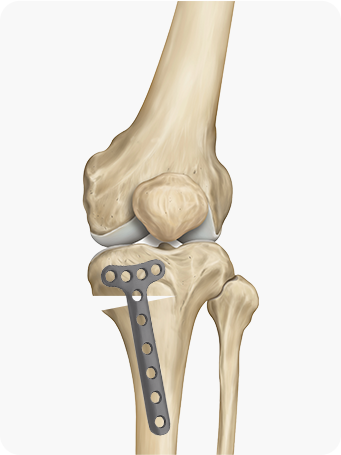

2

무게 중심이 외측으로

쏠려 있는 X다리 수술

교정 각도를 정밀하게 설계해 수술 계획을 세웁니다.

대퇴골을 절골하여 원하는 각도로 닫거나 벌려

무게 중심이 무릎 안쪽으로 옮겨지도록 교정

합니다.